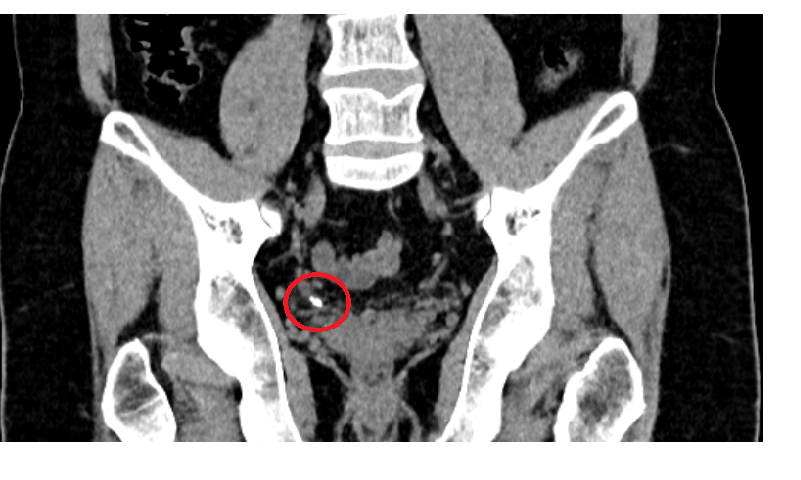

Сделал утром КТ по назначению уролога, так как месяц назад попал в неотложку с камнем в почке. Тогда на КТ он был 2х5мм, сейчас 3х7мм.

Но не в нем дело. А в других ярких точках в тазу (одна особо крупная и яркая), о которых в заключении радиолога ни полслова.